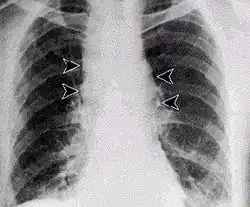

Antraz pulmonar com alargamento do Mediastino

O carbúnculo pode entrar no corpo humano por três vias:[19]